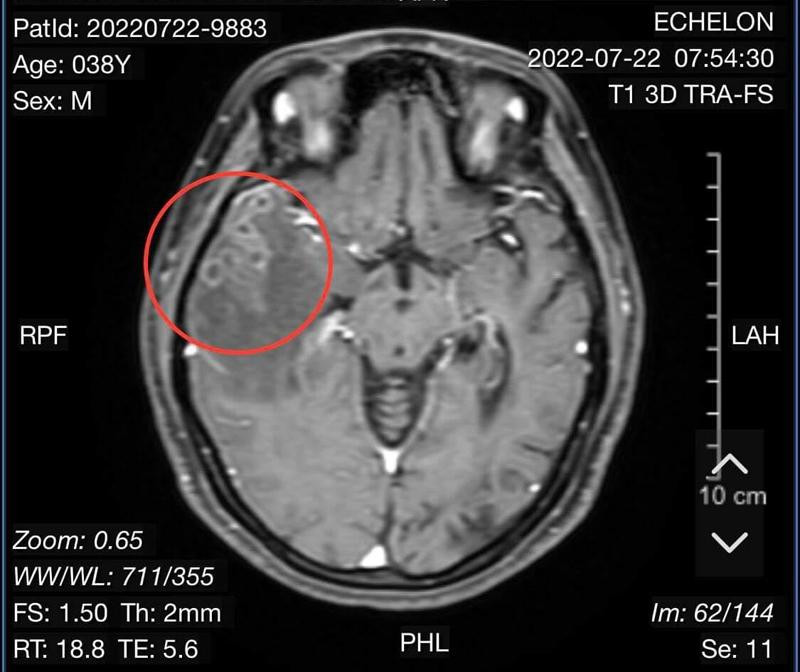

| Ảnh chụp cắt lớp não bệnh nhân và phát hiện ổ nang sán (Khu vực khoanh đỏ). |

Theo đó, vào ngày 20/7, bệnh nhân nữ H.T.L.A (SN 1984) trú tại phường Phước Long, TP. Nha Trang (tỉnh Khánh Hòa) có biểu hiện đau đầu dữ dội và được người thân đưa vào bệnh viện hữu nghị Việt Nam-Cu ba Đồng Hới. Qua thăm khám chụp cổng hưởng từ sọ não có tiêm chất tương phản cho thấy, người bệnh bị tổn thương não do sán. Kết quả xét nghiệm giải phẫu bệnh viêm não do nang sán.